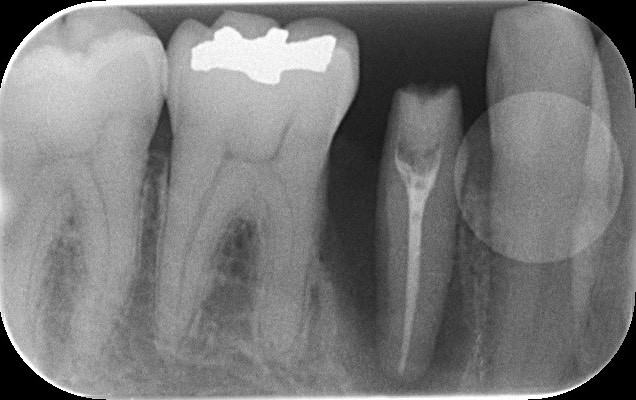

レントゲンでみると右下5番目(実際は左下5)の歯根の先端が黒く抜けています。この状態は、重度歯周病と根尖性歯周炎(根が膿んでる)が混在しており非常に予後が悪いとされています。

術前術後のレントゲンでの比較です。明らかに黒く骨欠損が著しかったところが、白く写り良質な骨が復活しているのがわかります。本症例では、骨補填剤は使っていないため全て自家骨での復活です。上顎両側4番目の歯は今後、インプラント治療を行っていく予定です。